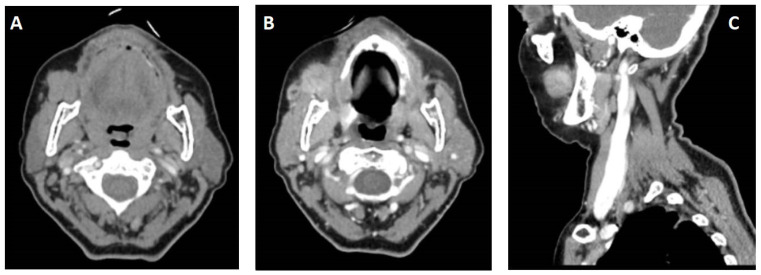

Case report: In this paper, we detail a case of PAC that developed in the buccal mucosa, which is a less common anatomical location. We discuss the patient's clinical presentation, imaging findings, histological examination results, as well as the surgical treatment and follow-up outcomes. We also examine relevant literature related to the topic to provide a comprehensive understanding of this rare case.